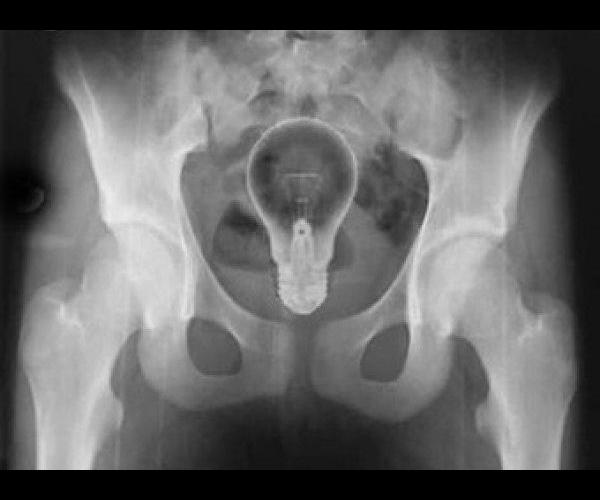

7. Une ampoule

Certains n’ont pas la lumière à tous les étages

ampoule

(source photo : Medisite)